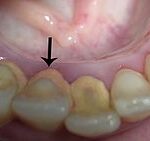

Tandsteen is tandplak dat lang tussen/op/naast je tanden heeft blijven kunnen zitten. Tandplak bestaat uit bacteriën, voedselresten en stoffen uit het speeksel. Als tandsteen lang blijft zitten, kan dit gaatjes (caviteiten) veroorzaken. De vraag is dus, hoe voorkom of verwijder ik het tandsteen? D

Heb je na het volgen van deze tips toch nog tandsteen? Dan zal het verwijderd moeten worden. Tandplak kun jezelf nog verwijderen, echter krijg je tandsteen zelf niet meer verwijderd met een tandenborstel.

Voor het verwijderen van tandsteen kun je een bezoek brengen aan de preventie assistente of de mondhygieniste. Zij verwijderen het tandsteen door middel van een sonde of een ultrasoon hulpmiddel (lostrillen van het tandsteen). Na het verwijderen van het tandsteen, polijst de assistente je tanden. Door het polijsten worden jouw tanden glad en op gladde tanden kan tandplak minder goed een houvast vinden.